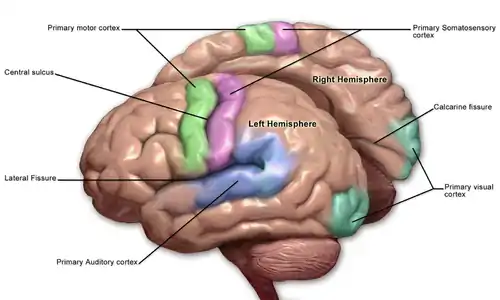

Sensory areas

The sensory areas are the cortical areas that receive and process information from the senses. Parts of the cortex that receive sensory inputs from the thalamus are called primary sensory areas. The senses of vision, hearing, and touch are served by the primary visual cortex, primary auditory cortex and primary somatosensory cortex respectively. In general, the two hemispheres receive information from the opposite (contralateral) side of the body. For example, the right primary somatosensory cortex receives information from the left limbs, and the right visual cortex receives information from the left visual field. The organization of sensory maps in the cortex reflects that of the corresponding sensing organ, in what is known as a topographic map. Neighboring points in the primary visual cortex, for example, correspond to neighboring points in the retina. This topographic map is called a retinotopic map. In the same way, there exists a tonotopic map in the primary auditory cortex and a somatotopic map in the primary sensory cortex. This last topographic map of the body onto the posterior central gyrus has been illustrated as a deformed human representation, the somatosensory homunculus, where the size of different body parts reflects the relative density of their innervation. Areas with much sensory innervation, such as the fingertips and the lips, require more cortical area to process finer sensation.

Motor areas

The motor areas are located in both hemispheres of the cortex. The motor areas are very closely related to the control of voluntary movements, especially fine fragmented movements performed by the hand. The right half of the motor area controls the left side of the body, and vice versa.

Two areas of the cortex are commonly referred to as motor:

- Primary motor cortex, which executes voluntary movements

- Supplementary motor areas and premotor cortex, which select voluntary movements.

In addition, motor functions have been described for:

- Posterior parietal cortex, which guides voluntary movements in space

- Dorsolateral prefrontal cortex, which decides which voluntary movements to make according to higher-order instructions, rules, and self-generated thoughts.